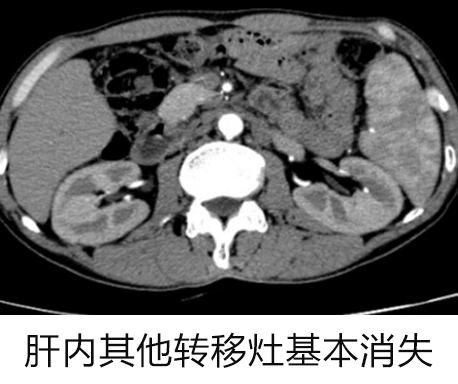

经过 5 个月的治疗后:

复查 CT 结果显示 肝脏左叶原发性肝癌介入栓塞术后病灶范围进一步缩小,AFP 指标也呈下降趋势。